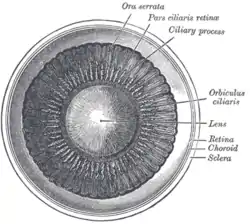

Schematic diagram of the human eye. | |

Position in the eye

The lens is located towards the front part of the vertebrate eye called the anterior segment which includes the cornea and iris positioned in front of the lens. The lens is held in place by the suspensory ligaments (Zonule of Zinn),[1] attaching the lens at its equator to the rest of the eye[2][3] through the ciliary body. Behind the lens is the jelly-like vitreous body which helps hold the lens in place. At the front of the lens is the liquid aqueous humor which bathes the lens with nutrients and other things. Land vertebrate lenses usually have an ellipsoid, biconvex shape. The front surface is less curved than the back. A human adult the lens is typically about 10mm in diameter and 4mm thick though changes shape with accommodation and size due to grow throughout a person's lifetime.[4]

Additional images

Section through the margin of the lens, showing the transition of the epithelium into the lens fibers known as the bow region. The structures of the eye labeled

The structures of the eye labeled Another view of the eye and the structures of the eye labeled